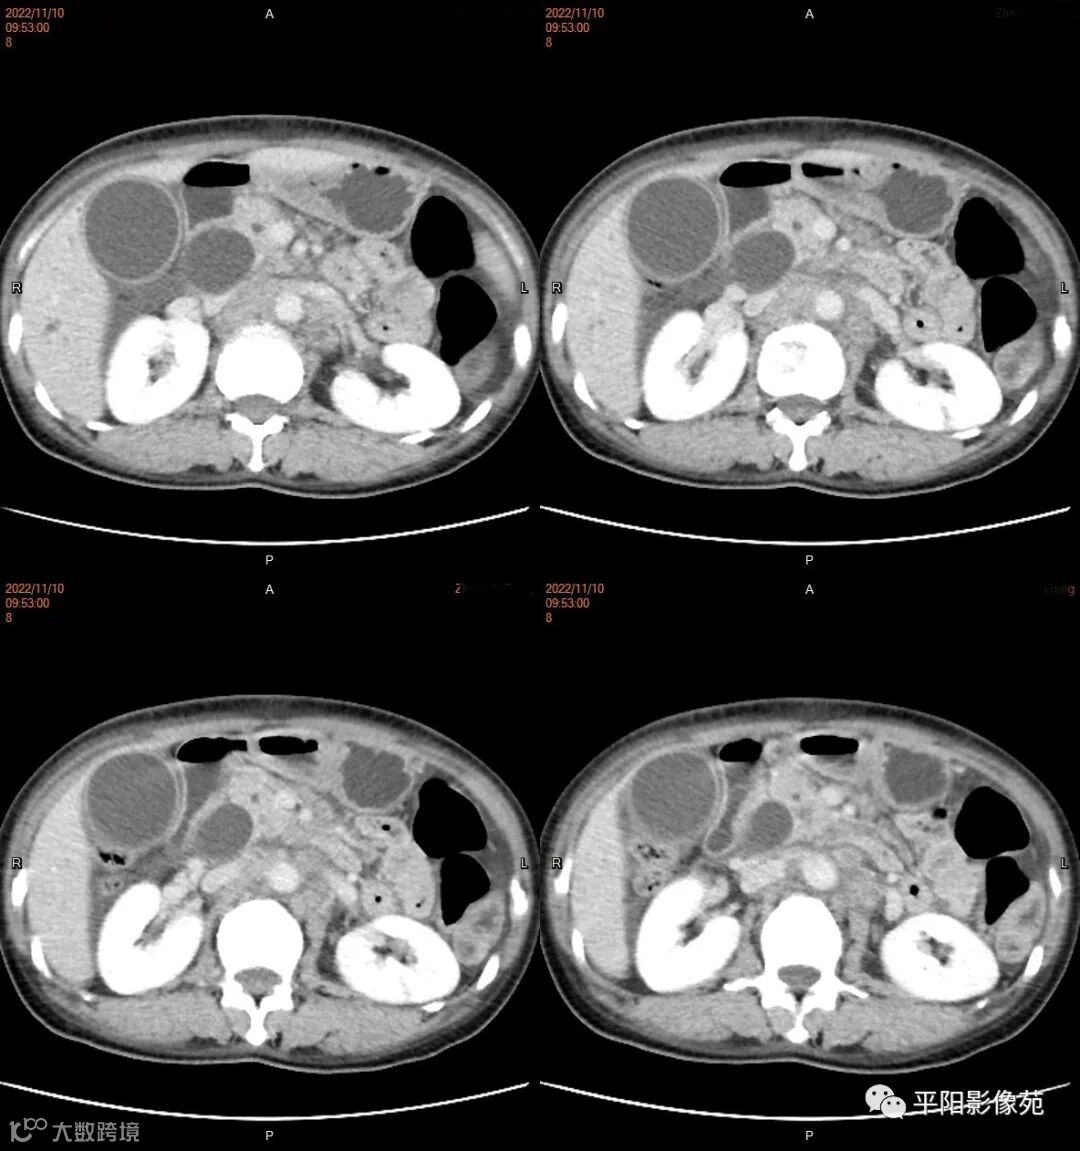

影像学检查

CT

肿瘤病理基础以肉眼形态分型可分为息肉型、溃疡型、缩窄型、弥漫狭窄型。

影像表现: